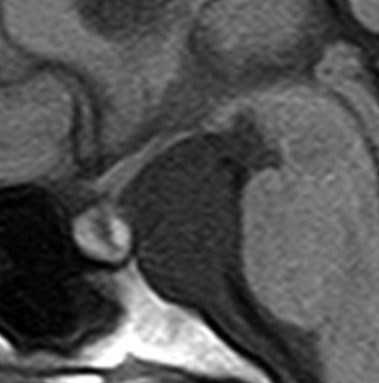

典型的な神経腸嚢胞 neurenteric cyst

左のT2強調画像で等信号,中のT2*で高信号,右はCISS画像です。

T1強調画像では,のう胞周囲の高信号の部分は半固体で,中心部の高信号はドロドロの粘液でした。基本的にガドリニウム増強はされません。まれに薄い膜状に一部が増強されることがあります。

境界明瞭は袋状の腫瘍です。椎骨動脈や脳底動脈を包み込むようにふくらんでいます。

左外側後頭下開頭という小さな開頭手術だけで全摘出しました。術後は幸い何の症状も出ていません。この例は脳幹部に食い込まないもので,運良く全摘できたのですが,そうはいかないものもあります。